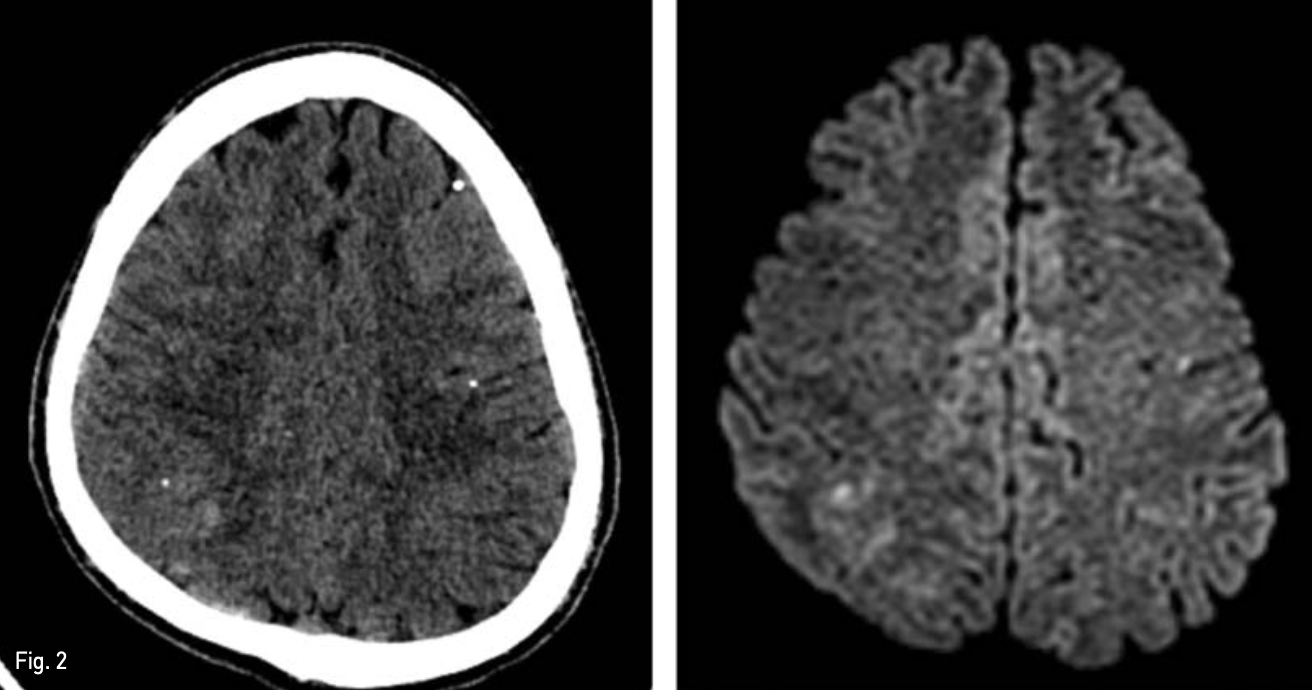

색전술 시행 후 환자는 심한 두통 및 양측성 시야 결손을 호소하였고, 색전술 시행 1일 후 추가적으로 촬영한 brain CT 및 MRI 상 다발성 급성 뇌경색 소견을 보였다(Fig. 2). 이후 보존적인 치료를 받으면서 환자의 모든 증상이 호전되었고 퇴원하였다.

An axial CT scan obtained 1 day following embolization, shows multifocal scattered lipiodol density in brain (left), and Diffusion weighted brain MR shows multiple diffusion restriction spot suggesting acute in farction (right).